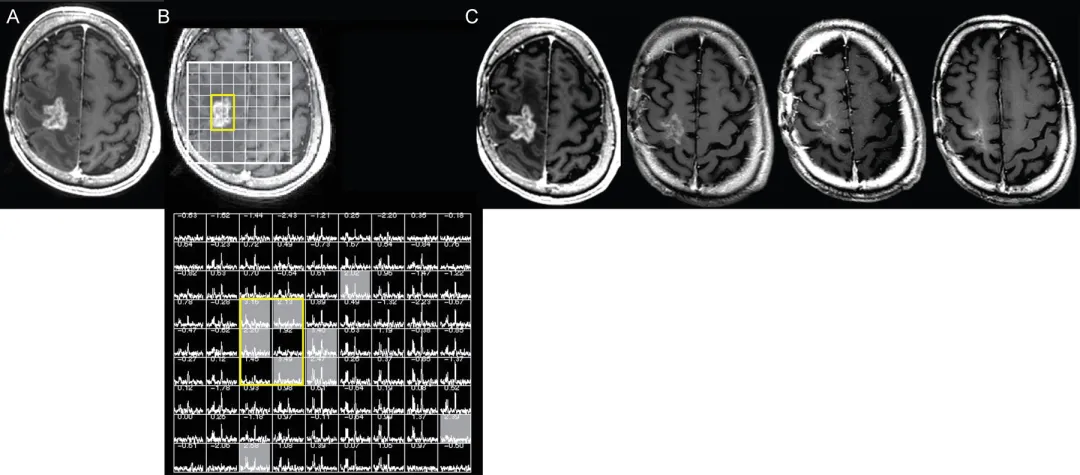

磁共振波谱成像

磁共振波谱成像(MRS)作为体素内代谢物标记的无创手段,也可辅助诊断真性进展。脑血容量与磁共振波谱方法的汇总分析显示,与假性进展相比,真性进展组的胆碱/N-乙酰天冬氨酸比值与胆碱/肌酸比值显著升高。确定合适截断值存在挑战,有研究报道采用对侧脑组织胆碱/胆碱比值的敏感度低至33%,而其他研究报道敏感度与特异度均超过90%。此外在强化区域内,对侧脑组织肌醇/肌酸比值降低与乳酸/谷氨酰胺+谷氨酰胺比值升高均与真性进展相关。磁共振波谱的局限性还在于其对异常区域体素定位的依赖,根据磁共振场强差异,获得足够信噪比所需的体素尺寸为1-8立方厘米,限制了该技术检测微小病灶变化的能力。尽管磁共振波谱单独诊断效能因技术限制存在差异,但联合扩散/灌注加权成像可提高整体准确性已达成共识。

图4. 磁共振波谱辅助判定假性进展

右侧额叶胶质母细胞瘤放疗后12个月疑似复发

A:轴位T1加权增强MRI显示结节状环形强化占位伴坏死

B:病变三维质子磁共振波谱显示N-乙酰天冬氨酸与胆碱显著降低(黄色轮廓),提示治疗相关改变而非肿瘤复发

C:连续8个月的四幅轴位T1加权增强MRI显示强化病灶进行性缩小,治疗未改变